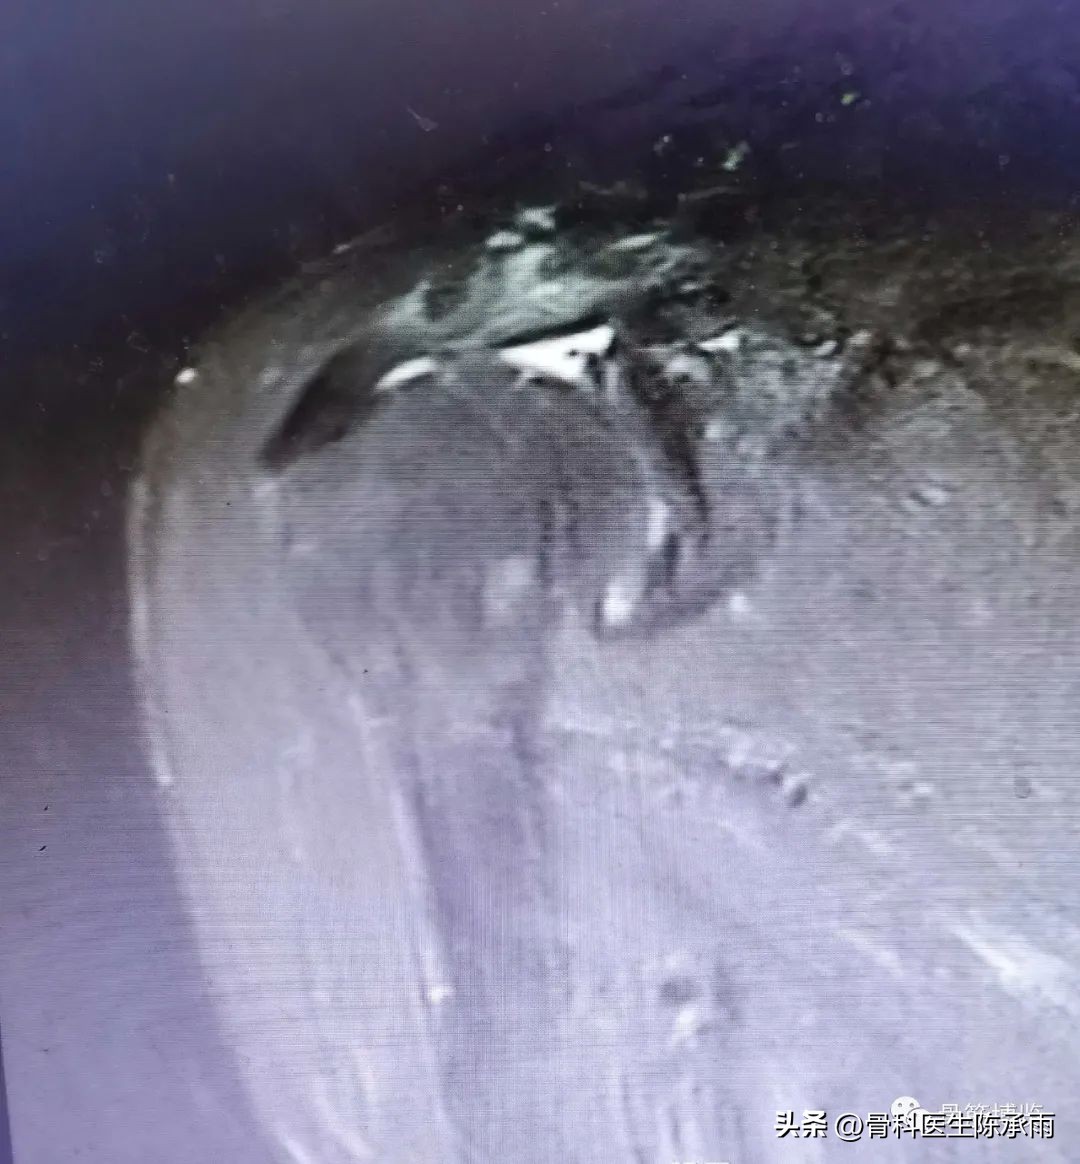

术中情况

术中探查肱二头 肌腱于止点处断裂,

同时行肩峰下成形

术中小切口于胸大肌下寻找到肱二头肌长头断裂的肌腱近端,引至结节间沟处,以1枚锚钉Onlay技术固定。